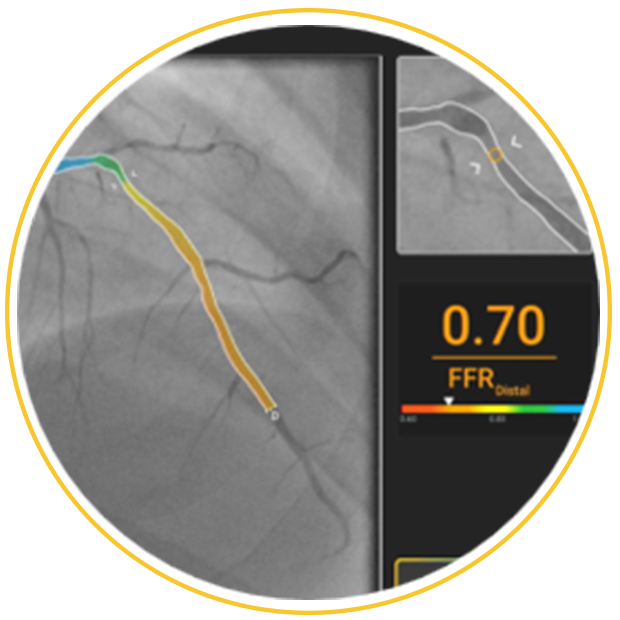

Clear Insights

FFR value and pressure curve along the selected vessel